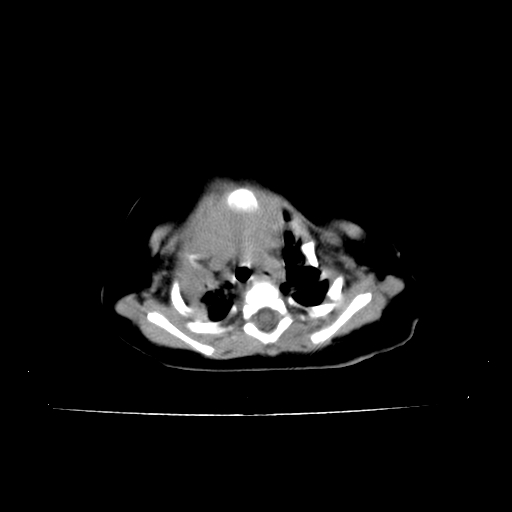

以下是引用影像之路在2009-5-8 15:46:00的发言:[br]1)胸廓畸形。2)考虑两肺感染性病变,并右肺上中叶肺不张;建议抗炎治疗后复查。3)胸腺肥大。4)前上中纵隔占位性病变待排;建议追踪复查。

以下是引用余辉在2009-5-8 8:44:00的发言:[br]鸡胸,胸腺肥大,双肺感染性病变,结合病史支原体肺炎可能性大